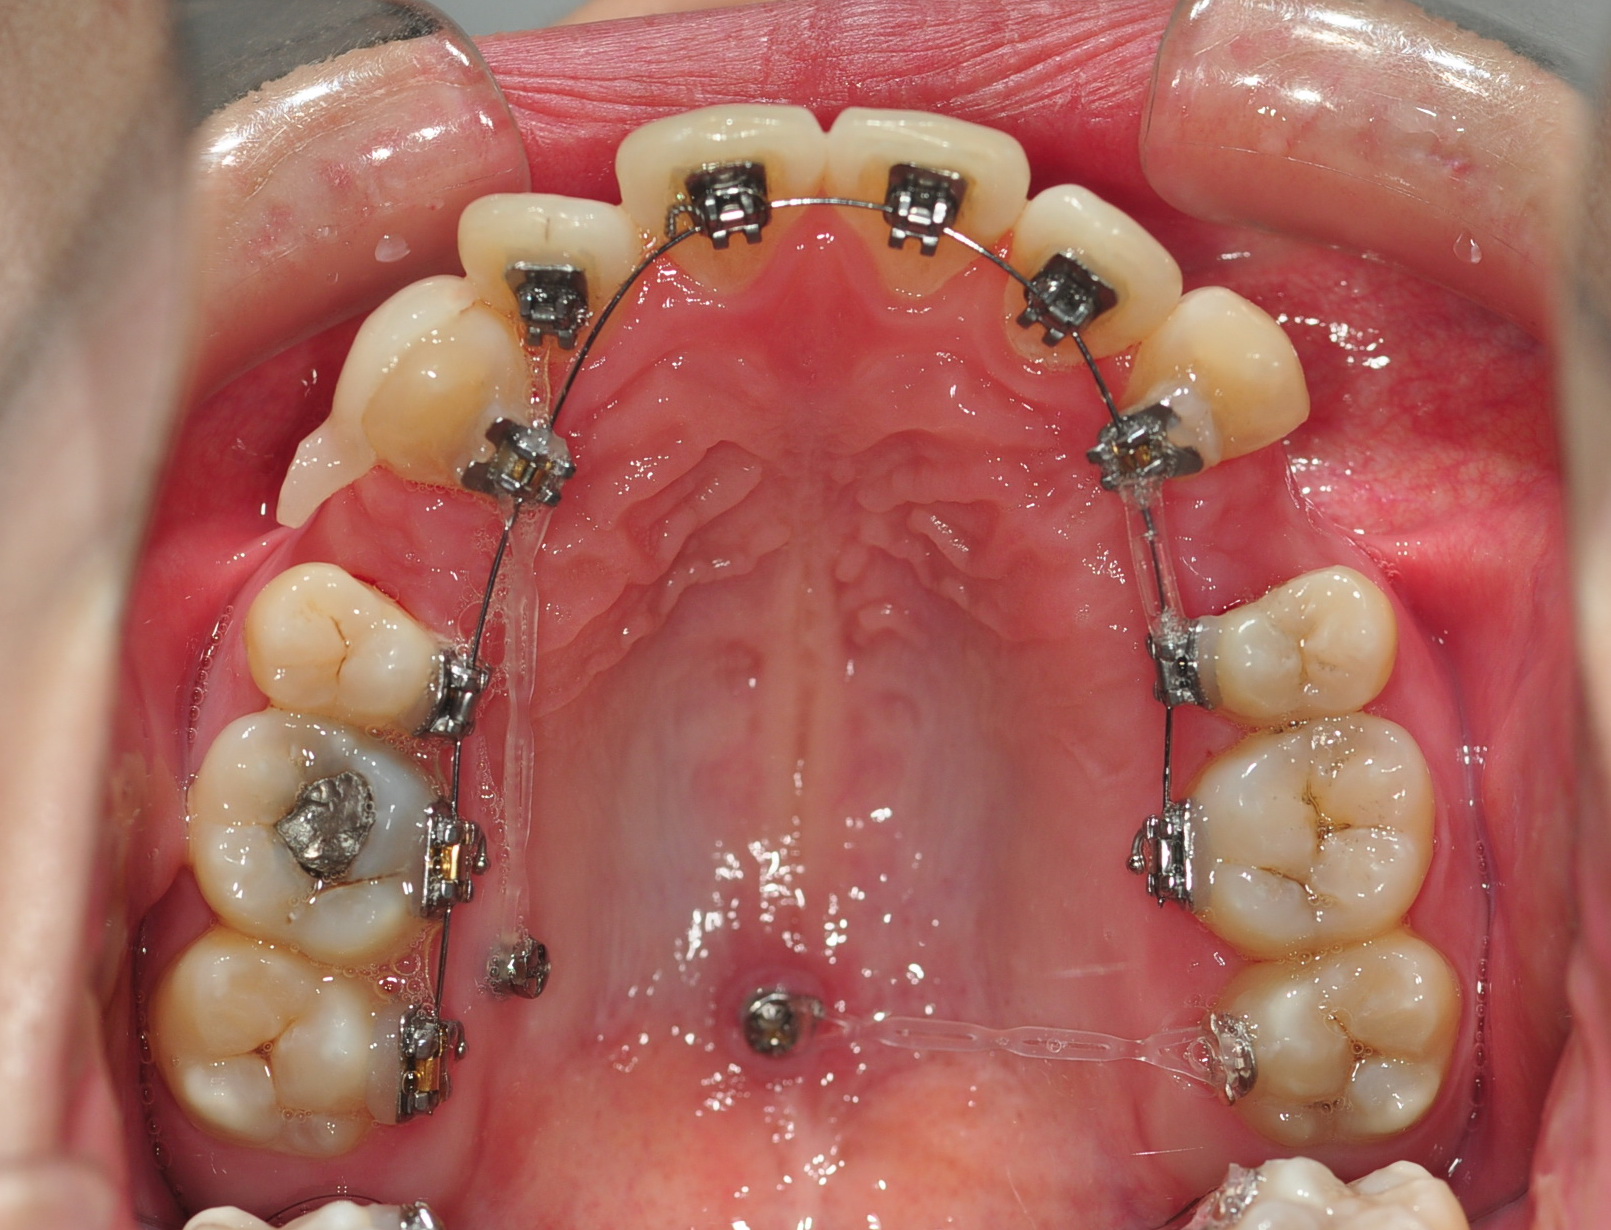

이번 오라픽스 치아교정 치료는 고무줄을 파워체인으로 교체하는 것과

상악에 심어두었던 스크류와 상악어금니를 연결하는 치료를 하였어용

두달 전쯤 치아교정 장치 브라켓이 떨어졌던 어금니와 연결하였답니당